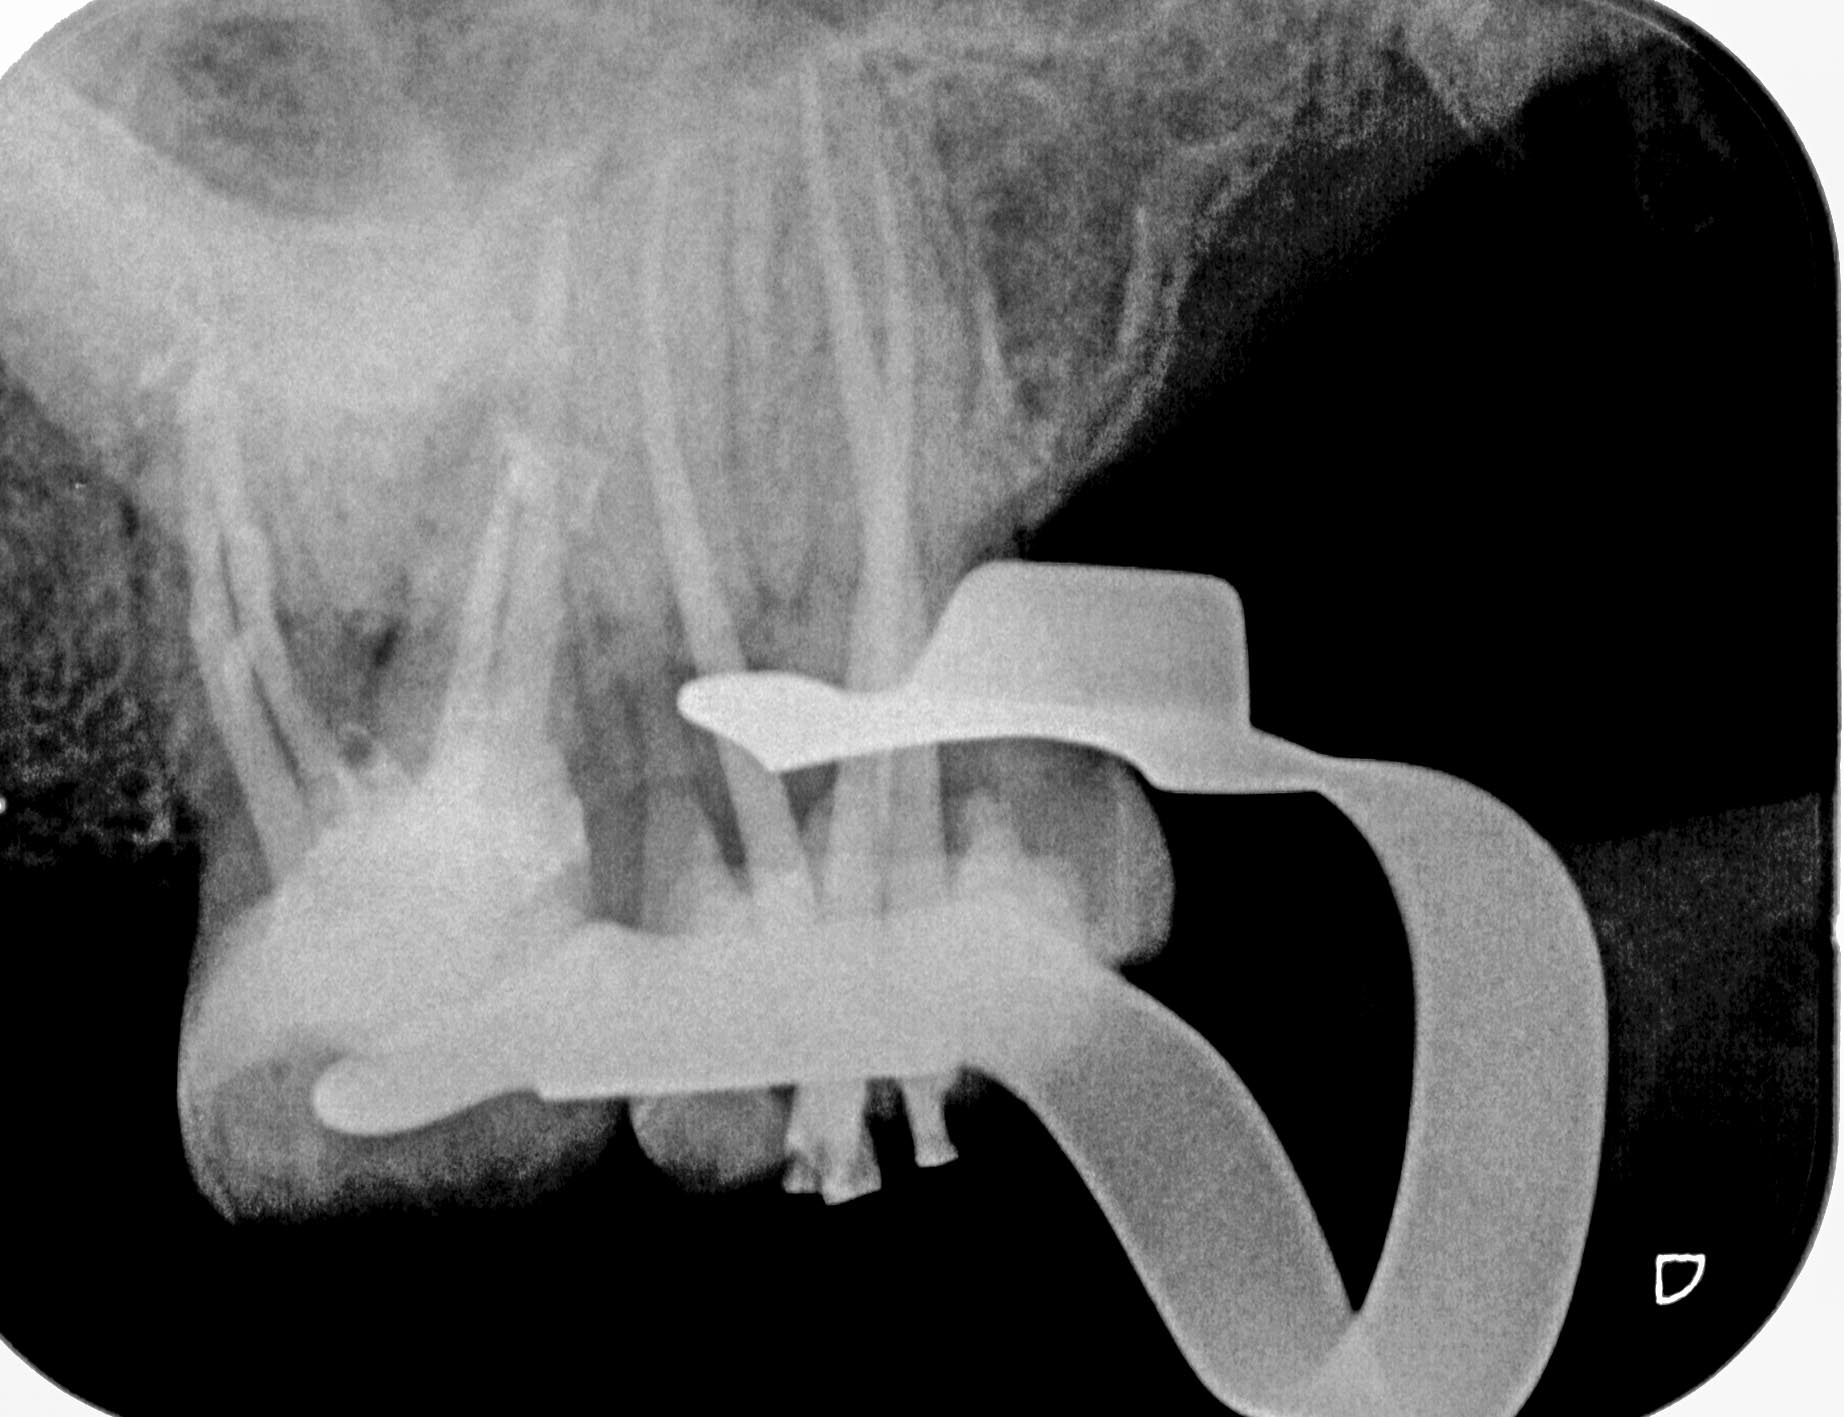

BN2627_1a-1-8 Veröffentlicht 1. Dezember 2014 am 1844 × 1417 in Unerwartete Anatomie Zahn 26, 27- die WF